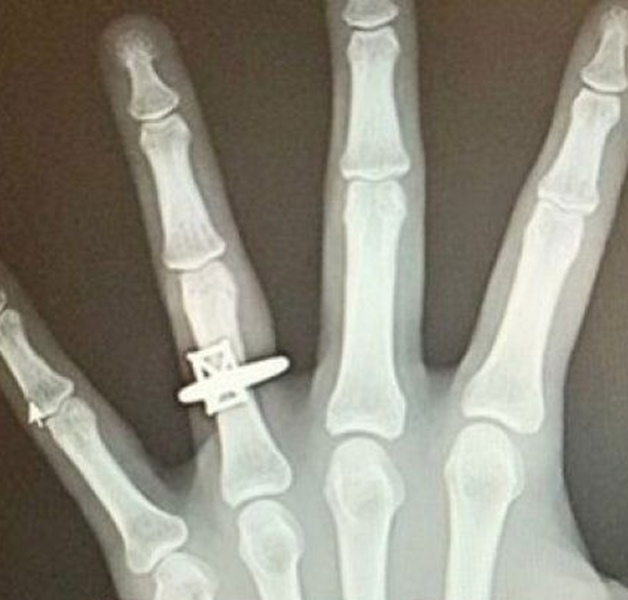

27岁的女子安娜伊斯原本以为手腕伤势严重,才惊动了急诊室多名医护人员围观,岂料当医生转过电脑萤幕,X光片上赫然出现的不是断裂的骨头,而是一枚戴在左手无名指上、闪闪发亮的钻戒影像。这场精心策划的“急诊室惊魂记”,最终在全院的欢呼声中圆满收场。

根据《时人》(People)报导,安娜伊斯是在返家途中不慎滑倒,于12日晚间在男友贾斯汀的陪同下前往布鲁克林CityMD急诊中心。当时她满心忧虑,纳闷为何解读小小的手腕X光报告,竟会吸引医生、护士及技术人员悉数到场。直到她盯着萤幕上那张别出心裁的“求婚版X光片”发愣时,31岁的贾斯汀已在身后单膝跪地,掏出那枚筹备已久的钻戒。

原来,贾斯汀是一名“行动派”,他早在一年前就开始物色这枚3.47克拉的鲜黄色钻戒。当女友受伤需要拍X光时,他敏锐地察觉到这是个千载难逢的时机,于是私下与急诊中心团队沟通,获得院方的全力配合。医护人员甚至利用影像重叠技术,在X光片中巧妙地“嵌入”了戒指的轮廓,给了安娜伊斯一个终生难忘的视觉冲击。